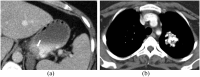

Hamartomas are tumours composed of mesenchymal tissues such as cartilage, fat, connective tissue and smooth muscle and can be found in virtually any organ system. These masses commonly develop sporadically, but are also seen in certain syndromes such as tuberous sclerosis or Carney triad. While their imaging appearance varies depending on the organ they arise from, findings are usually unique and a diagnosis can be confidently made. Radiologists must be aware of the clinical and imaging presentations of these lesions with the particular goal of avoiding unnecessary studies or invasive procedures. Furthermore, knowledge of common syndromic entities is crucial, as the radiologist may be the first to suggest the diagnosis.